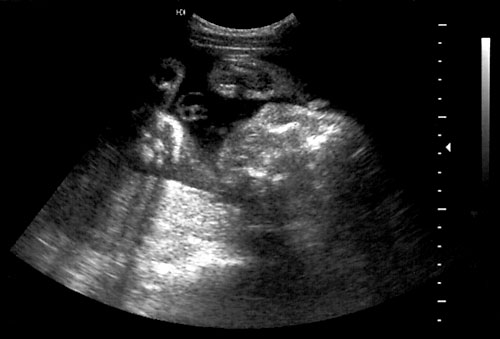

Normal diaphragm seen below right lung and above the liver in the middle of the picture with the hepatic veins diving below diaphragm. - Abdominal circumference.